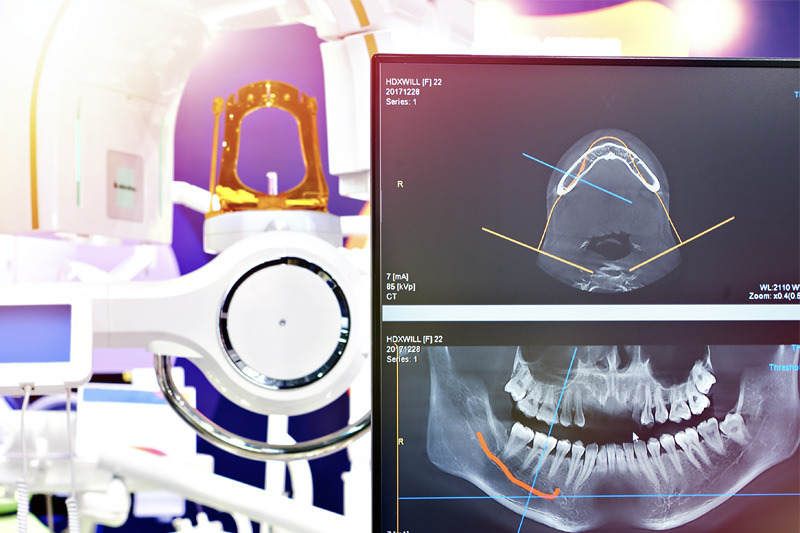

Learn MoreOur office has state of the art dental technology to provide you with the best possible dental care. See more below:

Cone Beam CT Imaging

Digital X-Rays